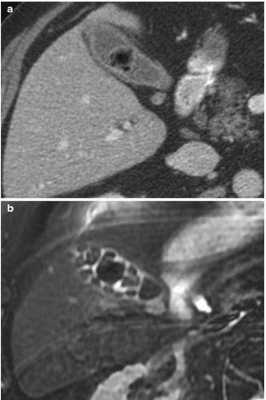

![Вид конкрементов у одного и того же пациента в желчном пузыре при КТ (а) и МРТ (b)]()

Вид конкрементов у одного и того же пациента в желчном пузыре при КТ (а) и МРТ (b)

КТ обнаруживает примерно 75% камней в желчном пузыре и протоках. Чувствительность способа зависит от состава конкрементов.

Результаты компьютерного сканирования не позволяют увидеть мягкие камни, но плотные конкременты визуализируются на томограммах хорошо.

Стандартом обследования при желчнокаменной болезни (ЖКБ) является ультразвуковая диагностика.

УЗИ и КТ - взаимодополняющие методы, компьютерная томография при ЖКБ выполняется для уточнения, нужна ли операция или нет (при холестериновых камнях достаточно консервативной терапии).